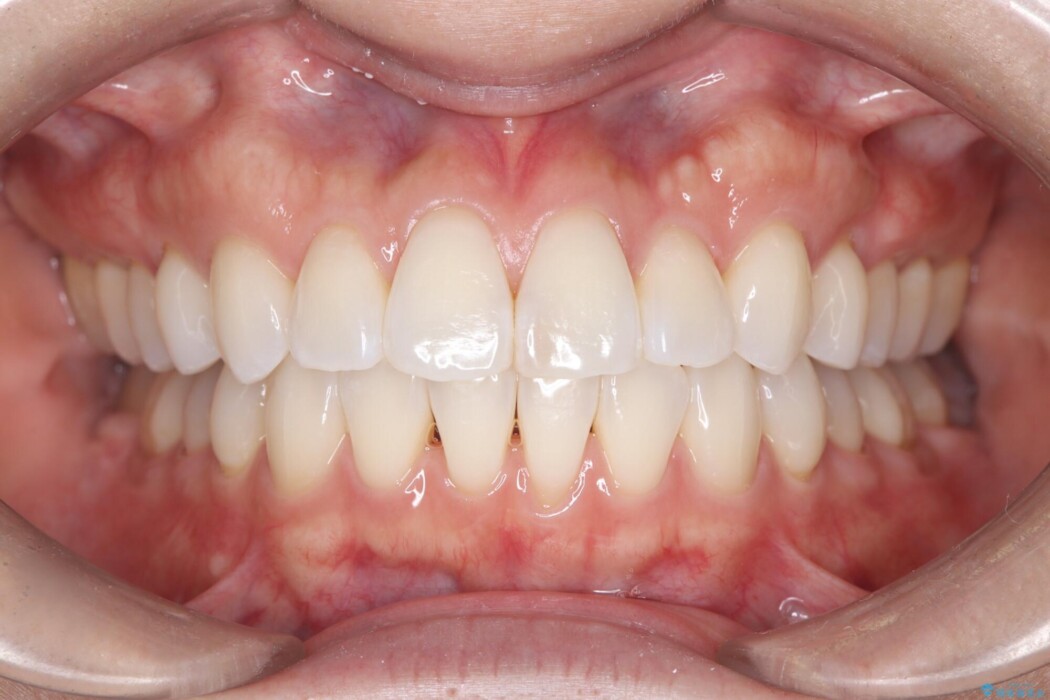

トランスパラタルアーチを用いて右上7番目の歯を内側へ誘導し、正しい位置へと修正しました。

まずはこの装置で奥歯の土台を安定させつつ、ワイヤー装置による繊細な歯の移動を組み合わせることで、非抜歯で歯列全体のアーチを整えていきました。シザーズバイトが解消されたことで、奥歯でしっかりと物を噛めるようになり、顎の動きもスムーズに改善されました。

治療完了後、前歯のガタつきはきれいに整い、上下の奥歯も理想的な位置で噛み合うようになりました。非抜歯での治療により、ご自身の歯をすべて残したまま、機能的で美しい歯並びを実現することができました。